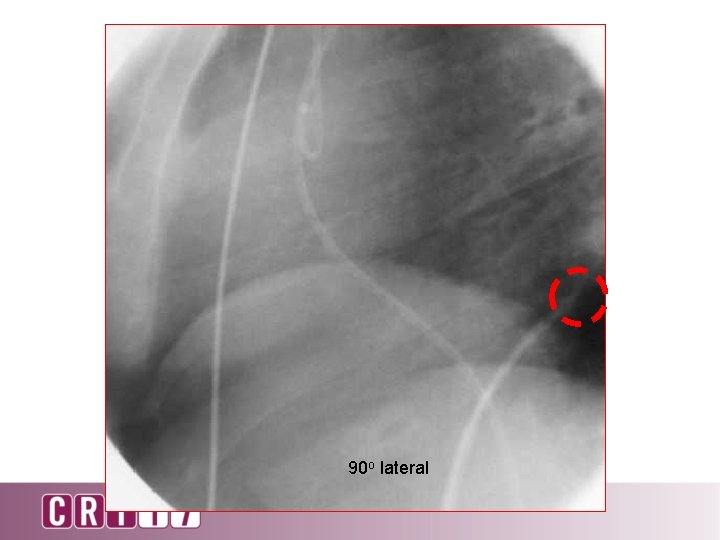

90 o lateral

90 degree lateral